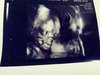

Ja wpadam sie pochwalić a nadrobie was wieczorkiem :) no więc tak syn dalej jest synem :D mowila ze widzi jajeczka i ze mu zwisa :D ale ogolnie mowila ze to za wczesnie na usg 3d ale zrobila :) takze ja jestem szczesliwa bo wiem ze serduszko bije i wszystko wporzadku :) caly czas sie ruszal nasz maly stworek hehe nogi ma strasznie dlugie :)

20180710_155638_Film1.jpg

20180710_155306_Film1.jpg

Załączniki

• 20180710_155638_Film1.jpg

1,2 MB · Wyświetleń: 318

• 20180710_155306_Film1.jpg

1,1 MB · Wyświetleń: 326